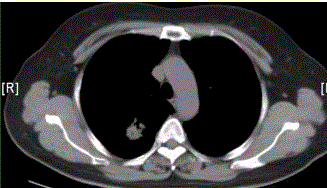

问题 患者女,54岁,无症状,常规体检透视时发现右上肺阴影。既往无结核病史。体格检查阴性。CT结果如下图。 局限性阻塞性肺气肿最常见的病因是

选项 A.支气管哮喘 B.支气管扩张 C.慢性支气管炎 D.大叶性肺炎 E.支气管肺癌 F.支气管囊肿

答案 E